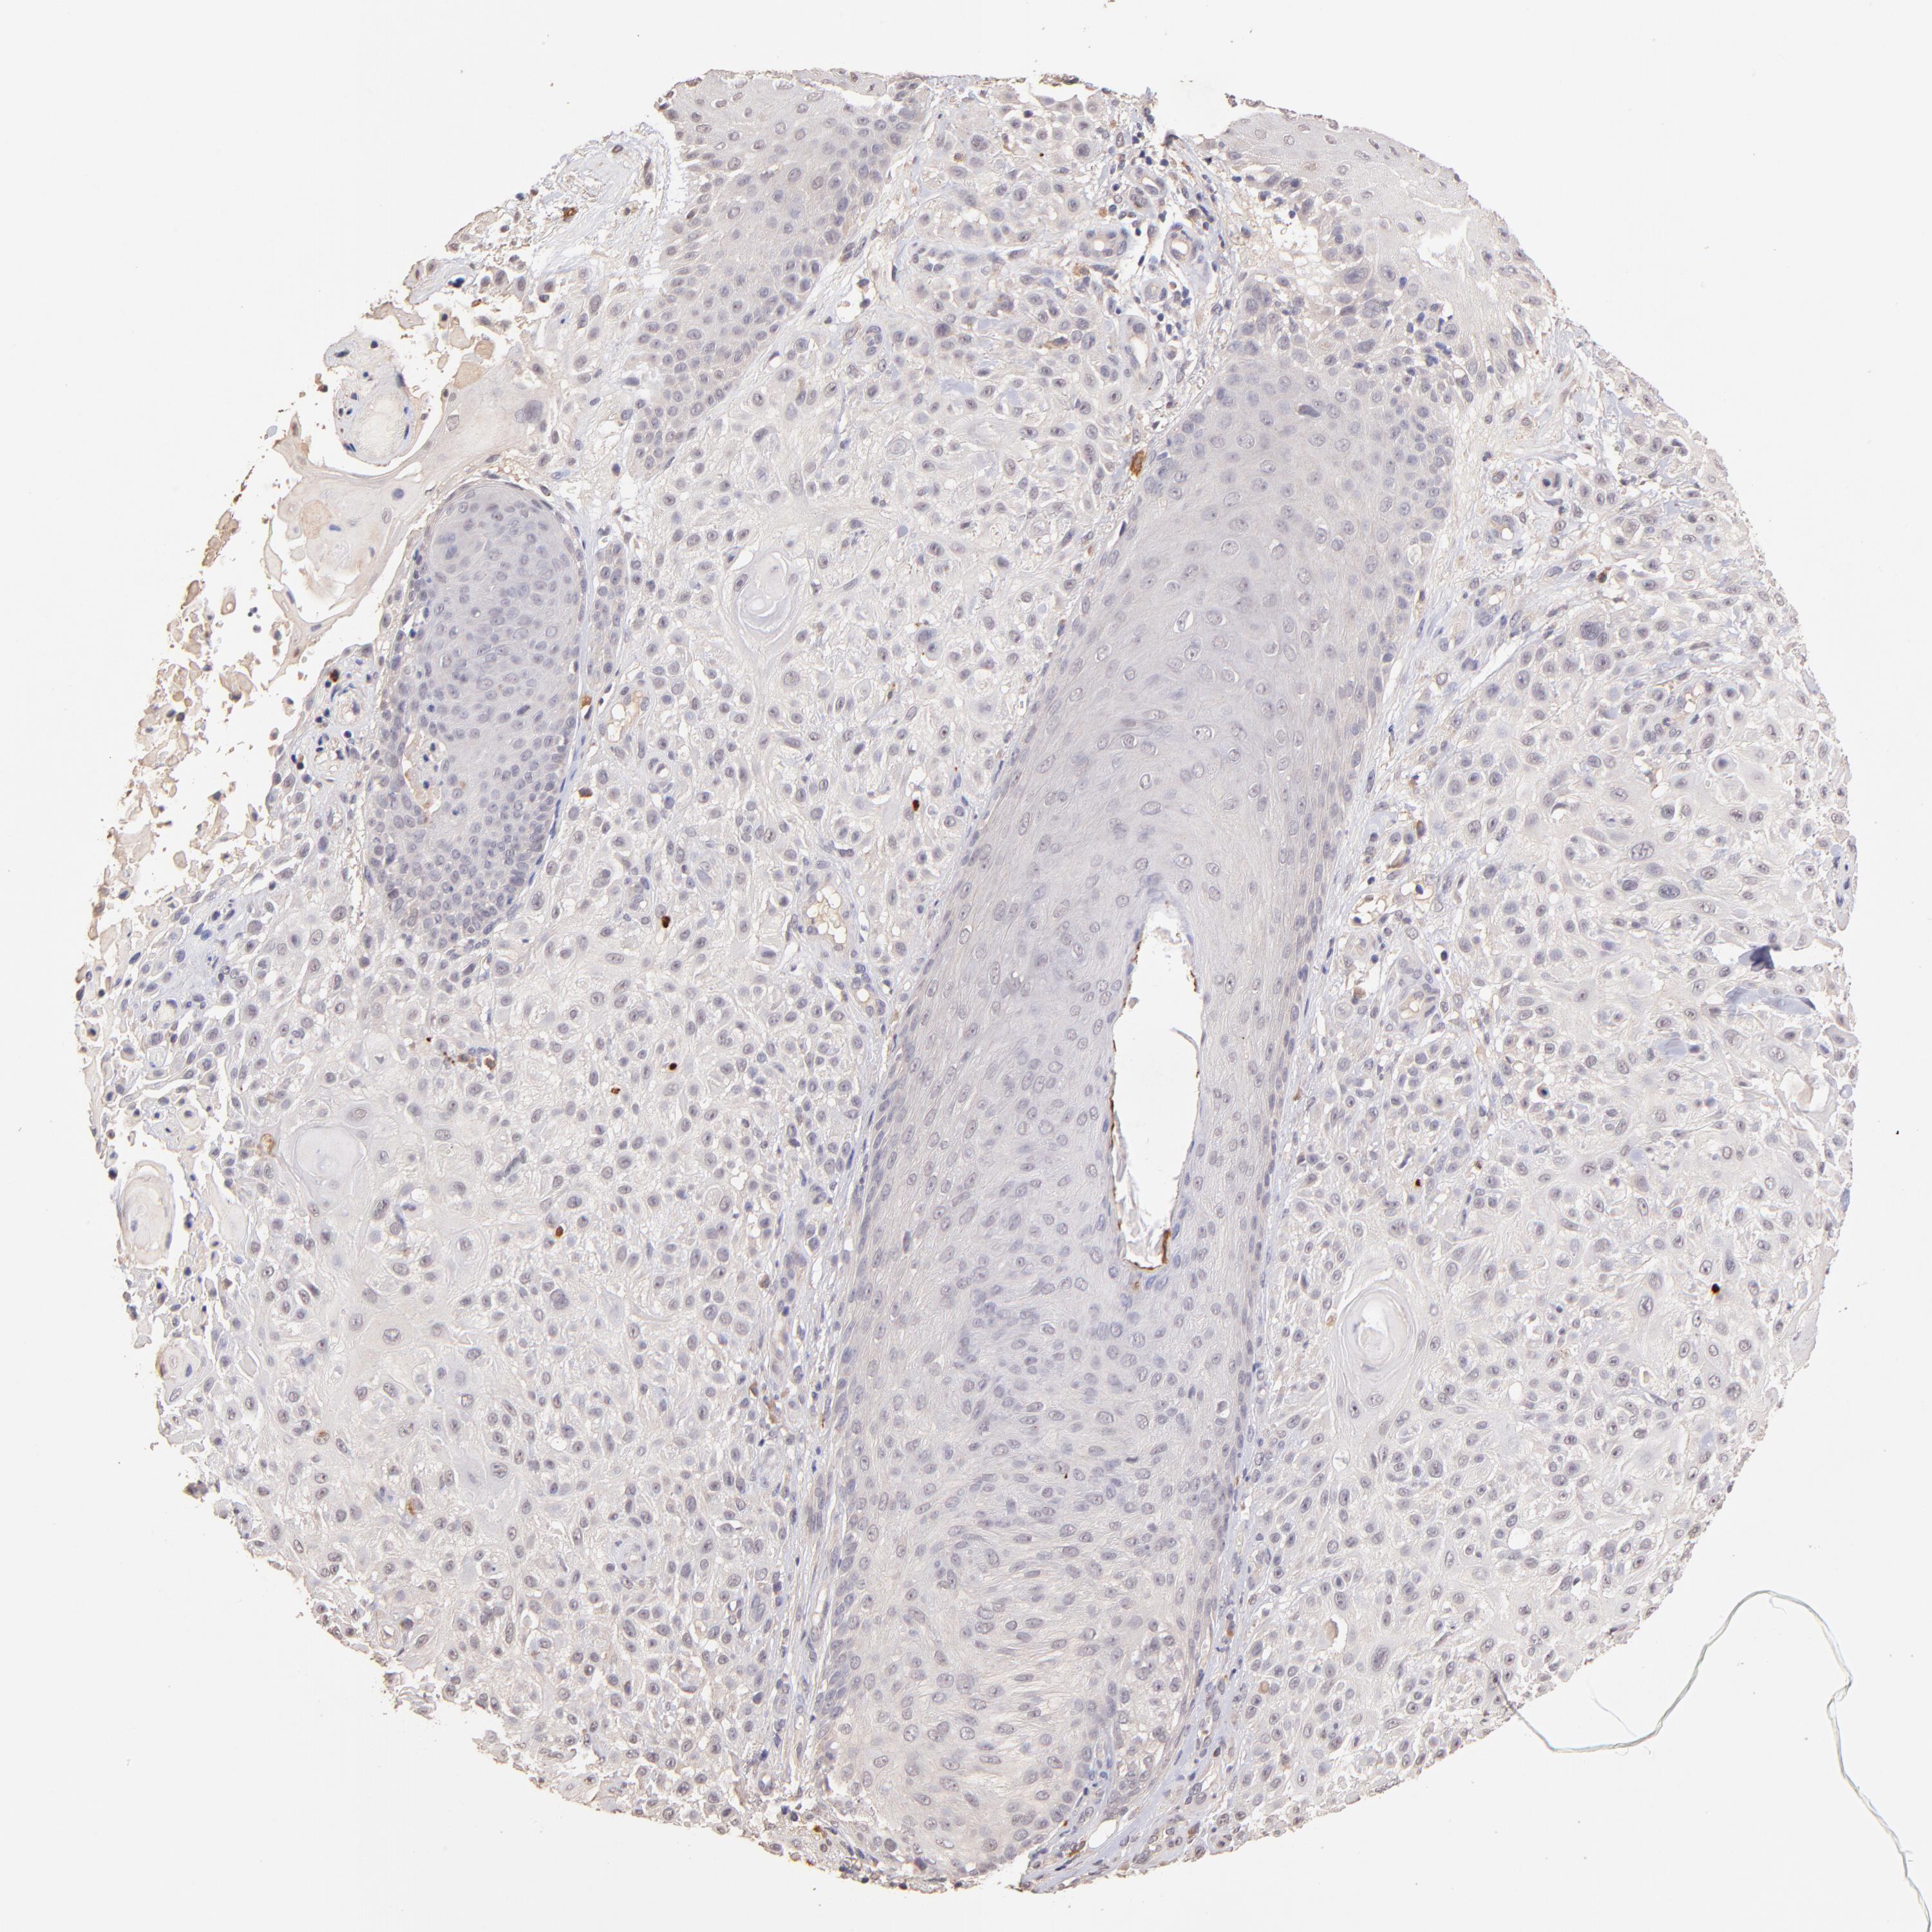

CANCER SKIN CANCER Show tissue menu

Basal cell and squamous cell cancer

SKIN CANCER - Protein expressioni

A mouse-over function shows sample information and annotation data. Click on an image to view it in a full screen mode. Samples can be filtered based on level of antibody staining by selecting one or several of the following categories: high, medium, low and not detected. The assay and annotation is described here.

Each image is clickable and will lead to virtual microscopy that enables deeper exploration of all samples and also displays staining intensity scores, fraction scores and subcellular localization as well as patient and tissue information for each sample.

Antibody CAB010906

Squamous cell carcinoma, NOS

Basal cell carcinoma